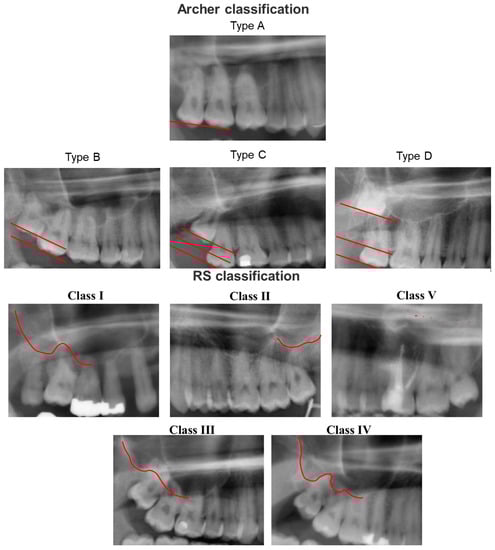

With advanced artificial intelligence (AI)-based approaches, decision making and problem solving can be automated [14]. The clinical decision process is generated by algorithms using the patterns found in the input data points. The incorporation of artificial intelligence into everyday clinical practice is becoming increasingly important in many medical specialties, as well as dentistry and oral and maxillofacial surgery [15]. A review by Khanagar et al. revealed an increasing interest in AI research in dentistry and oral and maxillofacial surgery [15]. Most of the papers listed in the review focused on the diagnosis of dental caries and other oral pathologies. Alveolar bone loss, the proximity of the third lower molar to the alveolar nerve, or the prediction of orthodontic extractions could be investigated for similar questions as in the present work [15]. The predictive assessment of OAC based on preoperative panoramic radiography has been investigated in our previous study [16]. Here, we found only limited comparability of AI-based results compared to experienced surgeons. Even between different AI algorithms, the results were not consistent. Relying on the prediction of an AI-based algorithm alone can thus not be conclusively recommended based on available evidence. Further studies with larger case numbers, other algorithms, and multicenter center studies might be necessary [16]. Several risk factors can be employed to predict the development of OAC. Besides factors such as age or gender, techniques such as the selected surgical procedure and the practitioner’s experience as well as anatomical conditions can influence the occurrence of OAC. For professionals and automated algorithms, standardized classification systems such as the Archer Classification [17] and the Root Sinus Classification (RS) [18] can be useful due to their reproducibility [19]. The Archer classification is based on the positional relationship of the third molar to the adjacent tooth and its relationship to the maxillary sinus, whereas the RS classification is dependent on the root tips as well as the direct relationship to the maxillary sinus floor (Figure 1) [19].

Figure 1.

Archer classification and Root Sinus (RS) classification based on panoramic radiography. Archer classification: Type A: the upper third molar is situated on the same or below the occlusal plane of its neighboring second molar. Type B: the upper third molar is located between the occlusal and cervical lines of the adjacent second molar. Type C: the upper third molar is located between the cervical line and the upper root third of the neighboring second molar. Type D: The third upper molar is located at the level of or above the apical third of the adjacent second molar. RS Classification: Class I: the maxillary sinus is located strictly above the root apex of the maxillary third molar. Class II: the line of the maxillary sinus floor is sharply curved and partially overlapped by the root apex of the maxillary third molar. Class III: the line of the maxillary sinus floor slopes sharply between the maxillary teeth and overlaps most of the roots. Class IV: the line of the maxillary sinus floor meets the root tips and slopes only between the root seats. Class V: the line of the maxillary sinus floor in relation to the root tips of the maxillary third molars cannot be reliably delineated.